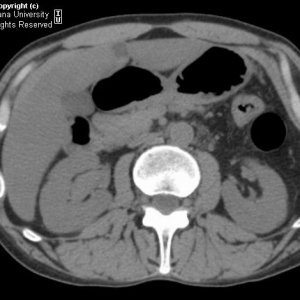

病例学习 肾盂移行细胞癌一例

ʱ: 2015-3-20 10:22

基本病史:男性,50岁,腰痛。行CT检查结果如下:影像学特征:在腹部CT平扫中可见右肾下极集合系统扩张,其内可见不均质稍高密度影,无尿路钙化高密度征象。注入对比剂后,上述病变静脉期表现如平扫相似,在延长期可 ...